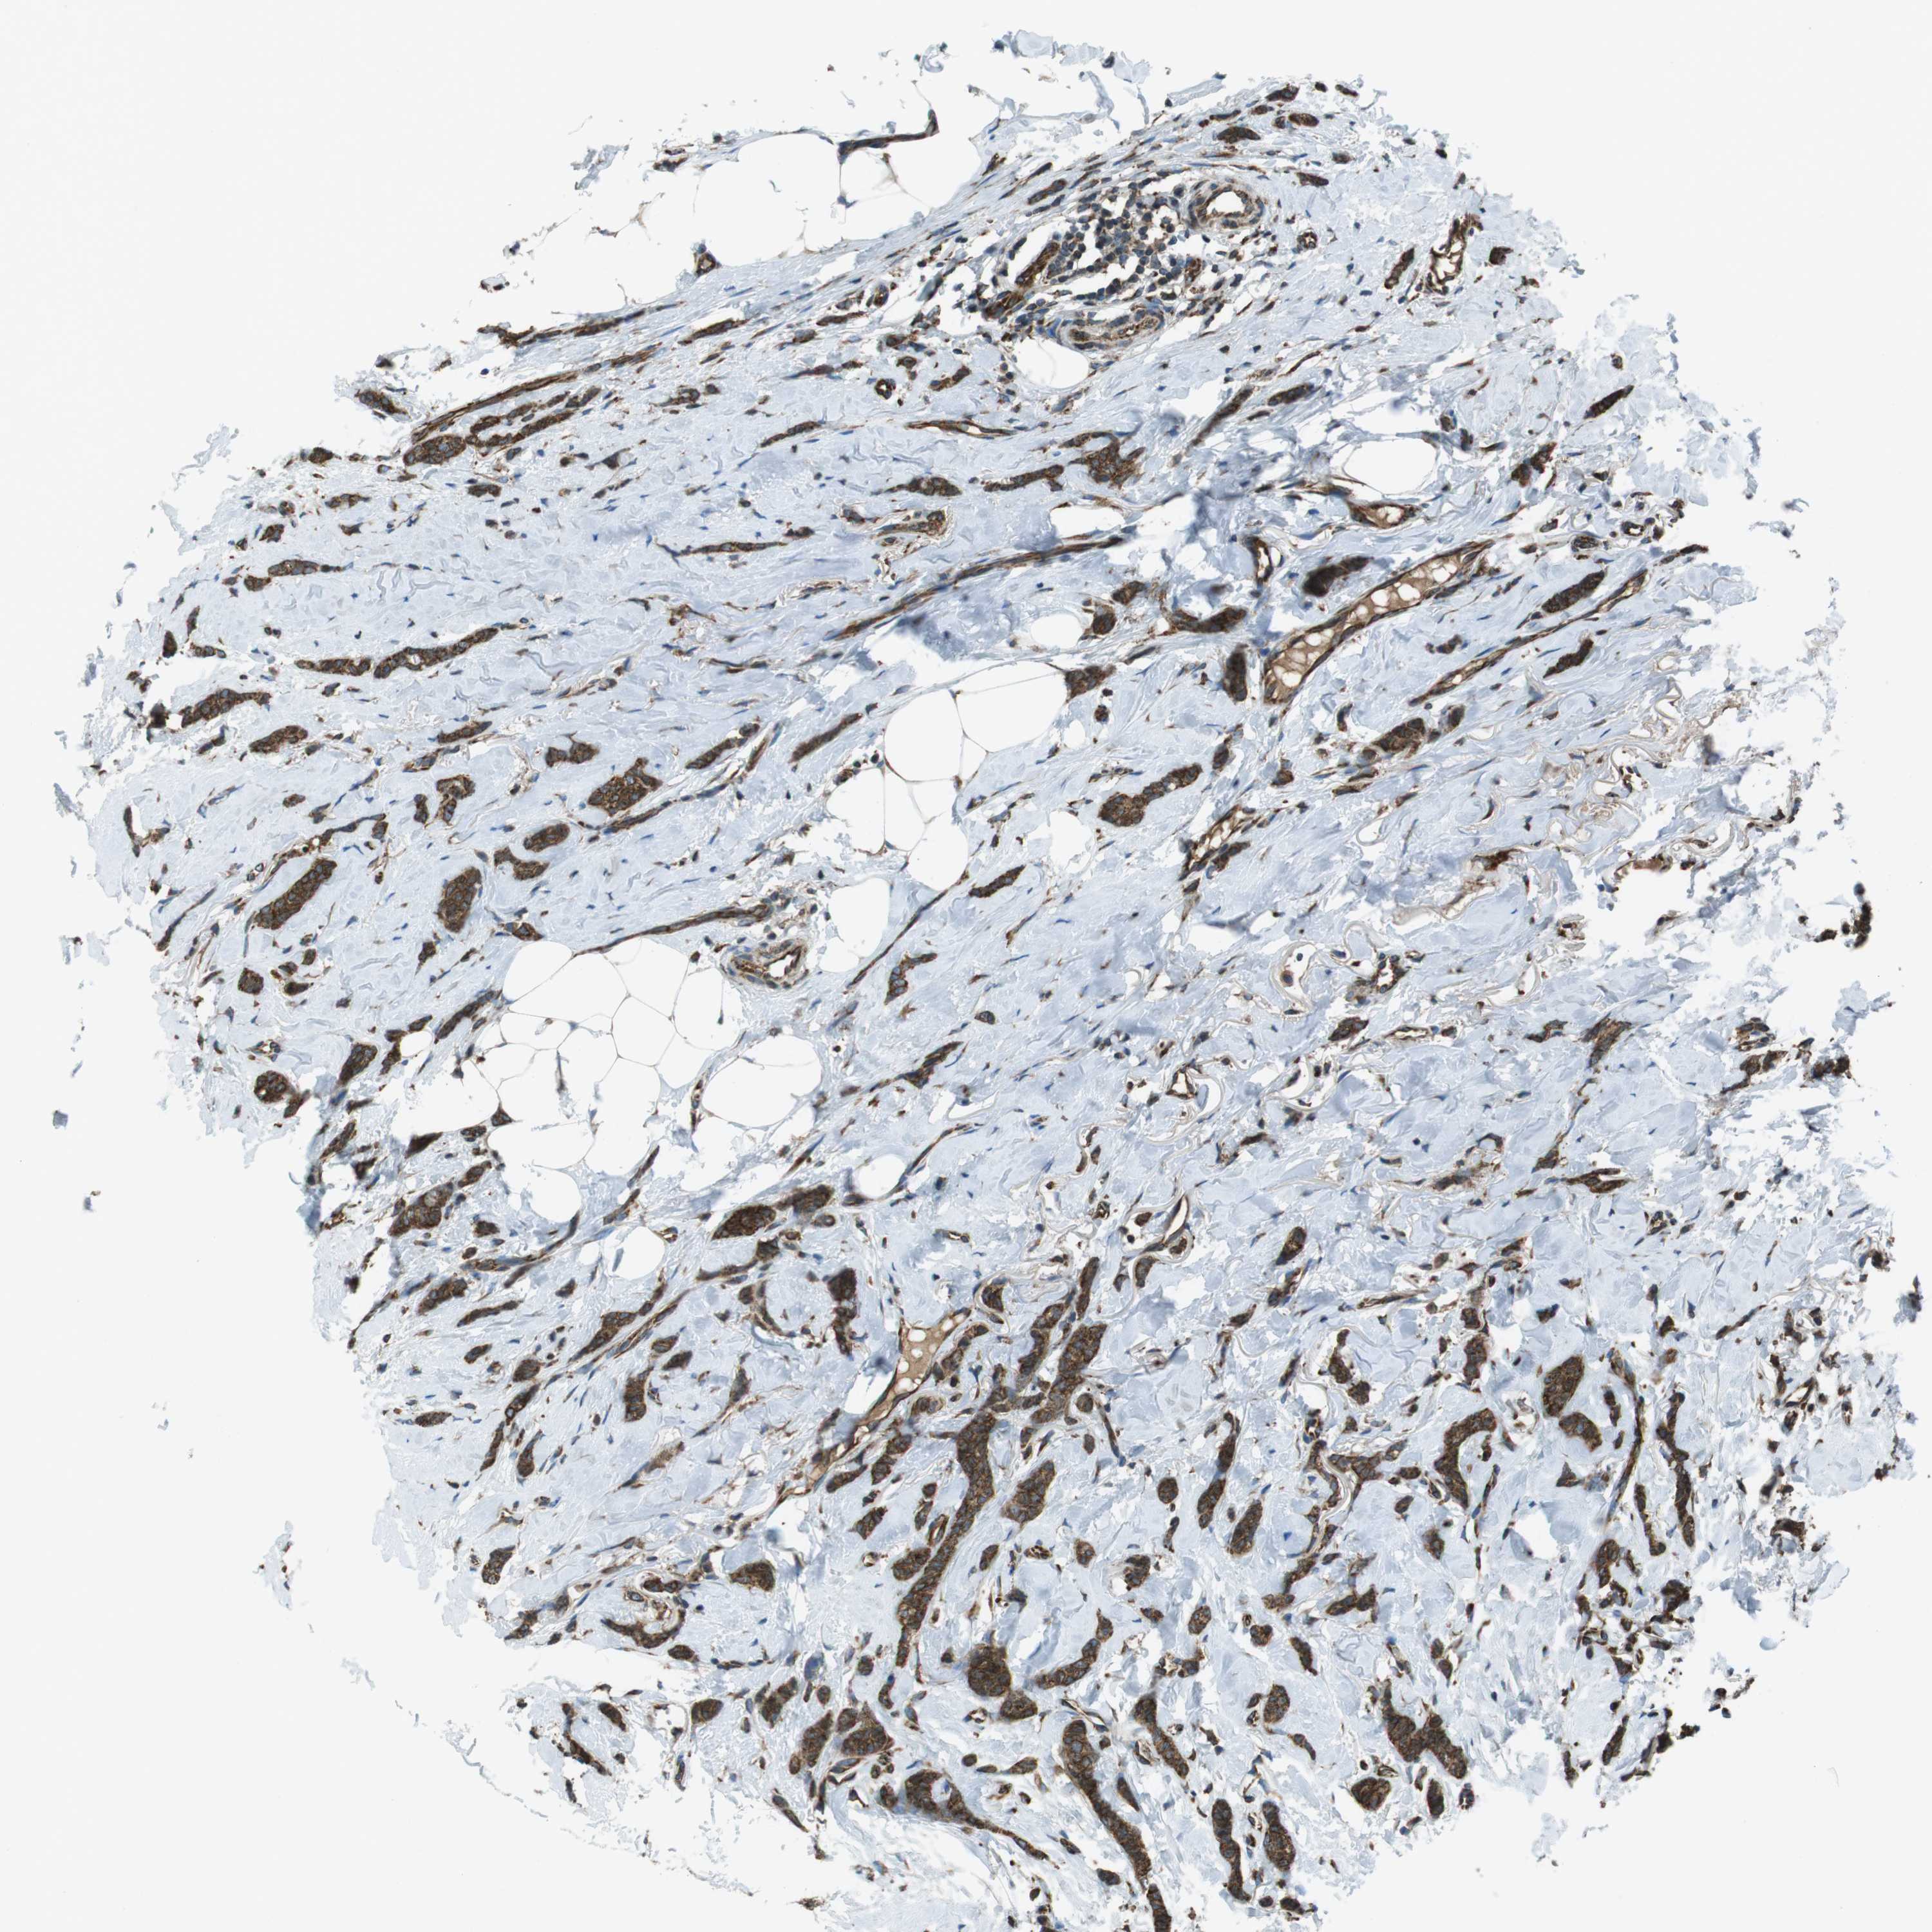

CANCER BREAST CANCER Show tissue menu

BRCA TCGA BRCA VALIDATION PROTEIN EXPRESSION